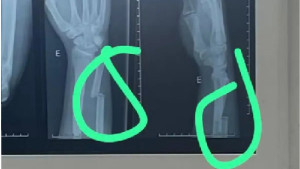

Jovem será submetido a cirurgia após agressão de policiais em Barra do Jacuípe, Camaçari